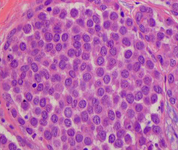

Histopatologia do carcinoma lobular in situ (CLIS) clássico

Cortesia da Dra. Sunati Sahoo, Universidade de Louisville; usado com permissão